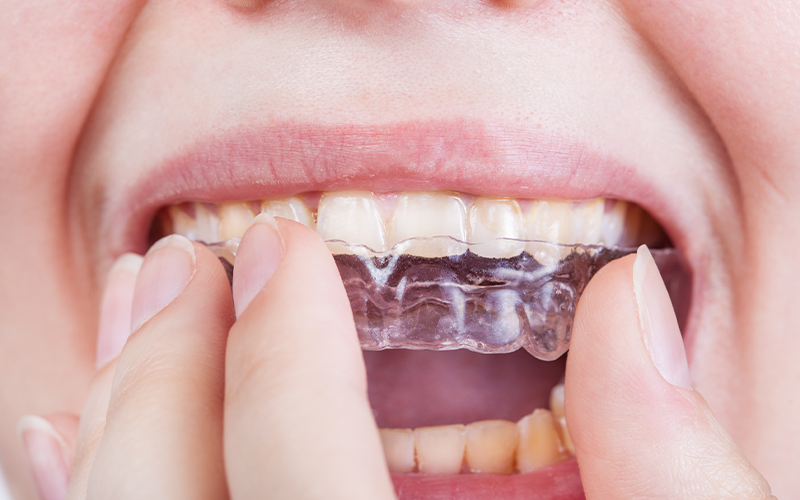

• 장치치료(스플린트)

서울바른훈치과 이갈이 치료방법

서울바른훈치과에서는 임상검사 및 바이트스트립, 필요시 치과에서 제작한 이갈이 검사장치를 이용하여 이갈이를 정확하게 진단하고 이와 동반된 치아시림, 턱관절장애, 안면부 근육통, 두통, 사각턱까지 총체적으로 치료가 가능합니다.

• 이갈이

방지장치